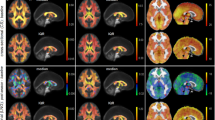

Importantly, none of the athletes recorded structural MRI abnormalities using conventional imaging metrics. A typical L-COSY spectrum from a healthy male with no history of brain trauma is shown in Figure 1A. This is compared to L-COSY data recorded from a professional male athlete of similar age and weight, with history of RBT, and with cognitive symptoms in Figure 1B. These representative spectra demonstrate well-resolved cross and diagonal peaks including amino acids: alanine, aspartate, isoleucine, leucine, lysine, taurine, threonine (Thr), phenylalanine (Phe); membrane phospholipids: glycerophosphorylcholine, phosphocholine, phosphoethanolamine; neurotransmitters: γ-amino-butyric acid (GABA), glutamate/glutamine (Glx); major metabolites: N-acetyl aspartate (NAA), choline (Cho), creatine (Cr), myo-inositol (mI), glutathione (GSH), taurine, lactate, multiple lipid resonances, and macromolecules.

L-COSY spectra. A) Age-matched healthy control; B) Athlete with history of RBT. Spectroscopy was performed at 3 T using a 32 channel head coil and voxel size of 3 × 3 × 3 cm3 in the PCG; increment size 0.8 ms; 64 increments with 8 averages resulting in an acquisition time of 12.8 minutes; acquired vector 1,024 points; acquisition time 512 ms; spectral width in F2 2,000 Hz and spectral width in F1 1,250 Hz. Assigned neurochemicals are according to Ramadan et al. [11] and Lean [21]. For presentation, the spectra were calibrated to the lysine cross peak at 3.00–1.67 ppm. Abbreviations: N-acetylaspartate (NAA), choline (Cho); creatine (Cr); glutamate (Glu) and glutamine together (Glx); aspartate (Asp); myoinsitol (mI); lysine (Lys); threonine (Thr), gamma-aminobutyric acid (GABA). L-COSY, localized correlated spectroscopy; PCG, posterior cingulate gyrus; RBT, repetitive brain trauma.

Large and significant differences in neurochemical levels were recorded when comparing age-matched RBT subjects to controls using non-parametric tests (P ≤0.05). Summarized in Table 3 and Figure 2 (scatterplot) are those cross peaks which are significantly different. Additional metabolites of interest such as NAA and mI (both have been shown to change in other traumatic brain injury (TBI) studies [23,24]) where changes were small or not statistically significant in this pilot series are also shown (Table 4).

The RBT cohort recorded an increase of 31%, 32% and 35% in the glutamine/glutamate cross peaks (2.09–3.75 ppm, 2.07–3.73 ppm and 2.14–3.74 ppm, respectively) (Table 3) when compared to controls. Figure 2 clearly demonstrates that for most of the Glx resonances there is no overlap between the RBT and control cohorts. It remains contentious as to whether glutamate and glutamine resonances are separable; thus, it cannot yet be ascertained if the increase is in glutamine or glutamate or both.

The methylene group of choline at 4.05–4.05 ppm was 65% higher in the RBT cohort. The scatterplot (Figure 2) shows that there is no overlap between the cross peak values measured in RBT subjects and controls. It is interesting to note that while the mean peak volumes of the choline resonances at 3.20–3.20 ppm and 3.51–4.05 ppm were greater, they were not statistically significant.

L-COSY also uniquely identifies additional resonances that cannot be characterized by one-dimensional MRS methods. For example, the cross peaks in the F2: 4.0–4.5, F1: 1.1–1.7 region, show a higher cross peak volume in molecules assigned to covalently linked terminal fucose molecules and threonine [21] of 60% in the RBT group [21]. The spectral region (F2: 4.0–4.5, F1: 1.1–1.7) contains threonine, fucose and, sometimes, lactate cross peaks. Originally assigned in the two-dimensional COSY from cultured cells [21,25] and more recently in vivo in the brain [11], these fucose cross peaks are also seen in the brain spectra reported by Velan et al. [14], but assigned to Thr/lactate alone. The assignment of bound fucose in the two-dimensional MR spectra was previously made using in vitro models by treating the cultured cells with fucosyl transferase and observing the bound cross peaks disappear and free α fucose at 1.22–4.21 ppm and free β fucose at 1.26–3.81 ppm appear [25]. It is the unique conformation of each of these terminal fucosylated species on the oligosaccharide chain on the cell membrane that generates the different chemical shifts for each fucose. Replicating this in a phantom is, thus, not possible [26].

An expansion of the aromatic region (F2: 6.00–9.00 ppm; F1: 6.00–9.00 ppm) where resonances [20] from phenylalanine (Phe; 7.33–7.33 ppm); imidazole from histamine and homocarnosine (Imi; 7.07–7.07 ppm); and high-frequency peak from NAA amine group and imidazole from histamine and histidine (HF; 7.82–7.82 ppm) on the diagonal are shown in Figure 3 as expanded from Figure 1. Phenylalanine was 46% higher in RBT subjects compared with controls and statistically significant.

An expansion of the aromatic region (F2: 6.00–9.00 ppm; F1: 6.00–9.00 ppm). Resonances from phenylalanine (Phe; 7.33–7.33); imidazole from histamine and homocarnosine (Imi; 7.07–7.07); and high-frequency peak from NAA amine group and imidazole from histamine and histidine (HF; 7.82–7.82) are on the diagonal. The data are again expanded from Figure 1. On the left are the results from the healthy control and on the right from the athletes with RBT, in which phenylalanine cross peaks are well visualized. There is a mean statistically significant greater phenylalanine by 46% in the RBT group as a whole. NAA, N-acetyl aspartate; RBT, repetitive brain trauma.